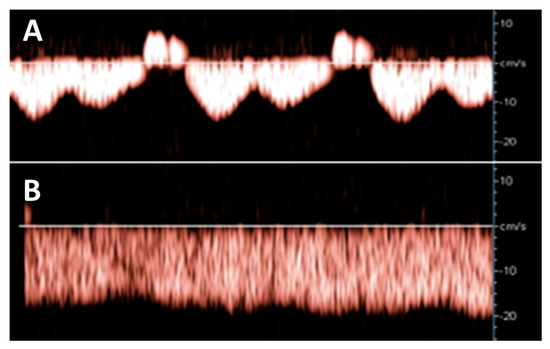

Hepatic venous Doppler ultrasonography showed a triphasic pattern of the hepatic vein before LAVH (Figure 4A), which abruptly shifted into a flat pattern during pneumoperitoneum-induced CO2 insufflation at IAP values at around maximum device controlled values of 14.7 mmHg (Figure 4B).

Figure 4.

Hepatic venous Doppler measurement was performed on two patients of the LAVH group. At the start of the LAVH procedure, a triphasic pattern was observed (A), changing into a flat pattern following pneumoperitoneum-induced IAP during the procedure (B). This shift is similar to the changes observed during the Valsalva maneuver [13], and during the course of pregnancy [17].